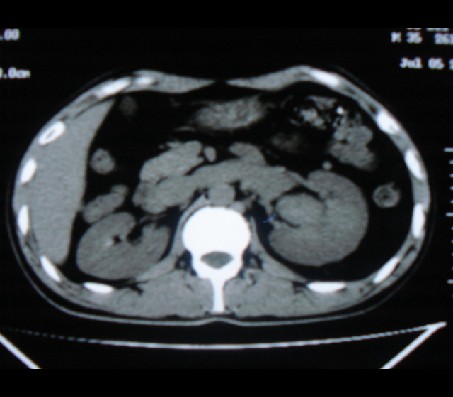

左肾癌侵犯肾盂可能性大,建议增强.

考虑左肾癌可能性大,建议增强扫描。

左肾癌侵犯肾盂可能性大。

肾癌侵犯肾盂,肾盂出血,肾盂内为血肿

首先考虑恶性肿瘤性病变,考虑左肾癌可能性大,建议增强扫描。